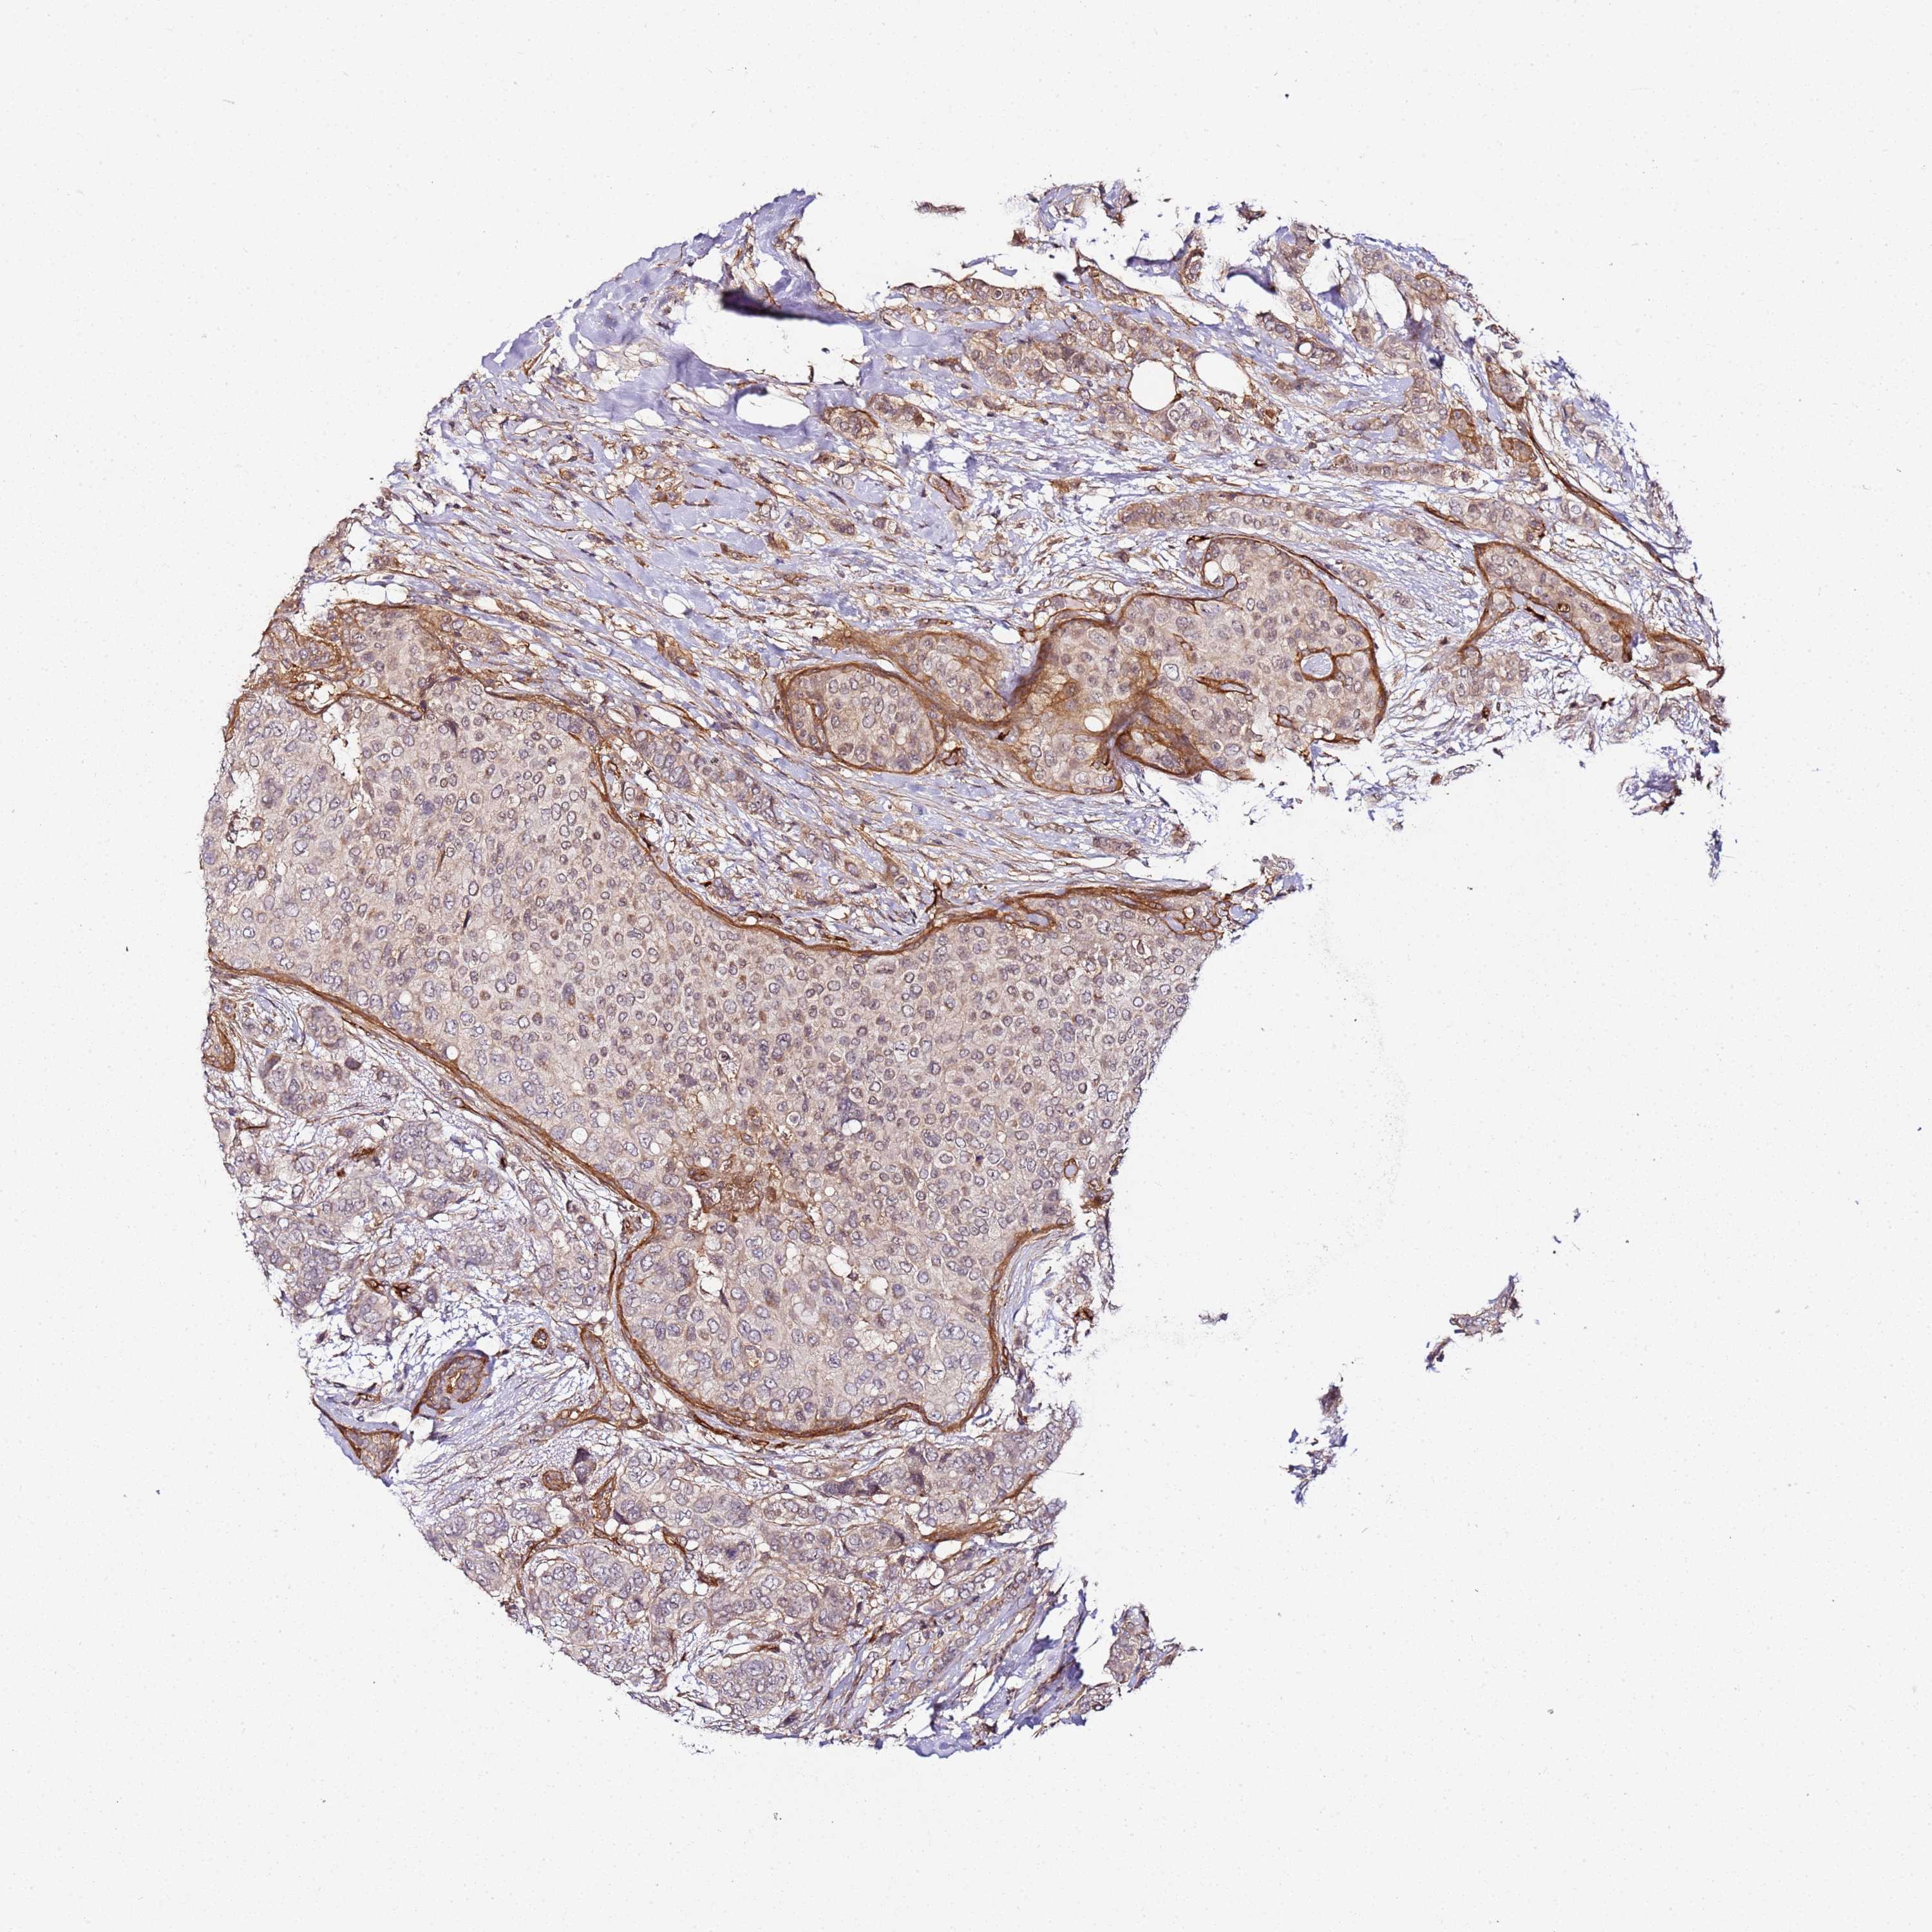

CANCER BREAST CANCER Show tissue menu

BRCA TCGA BRCA VALIDATION PROTEIN EXPRESSION